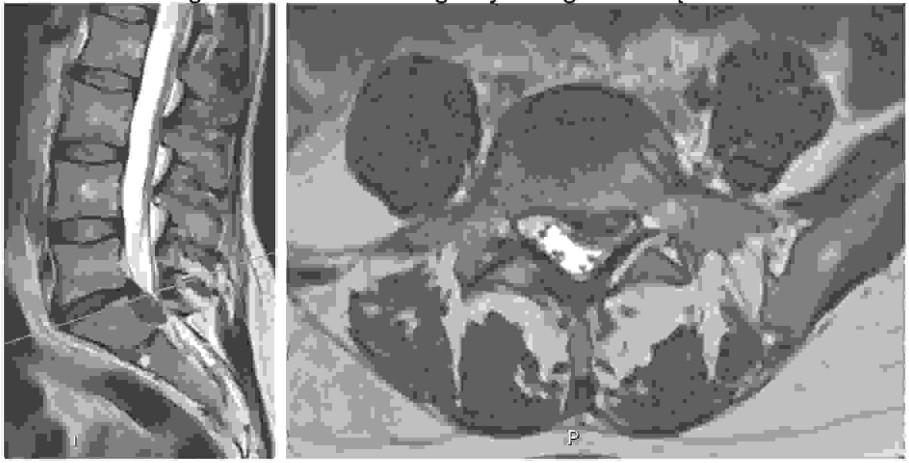

Do charakterystycznych objawów patologii widocznej na poniższych obrazach tomografii rezonansu magnetycznego należą: 1) osłabienie lub brak odruchu kolanowego, 2) ból promieniujący do kończyny dolnej wzdłuż przedniej powierzchni uda, 3) ból promieniujący do kończyny dolnej wzdłuż bocznej powierzchni uda, tylnej powierzchni podudzia, pięty, 4) osłabienie zgięcia podeszwowego stopy, 5) osłabienie lub brak odruchu ze ścięgna Achillesa.